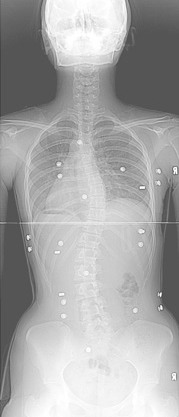

보조기 착용전

보조기 착용 후 교정된 모습